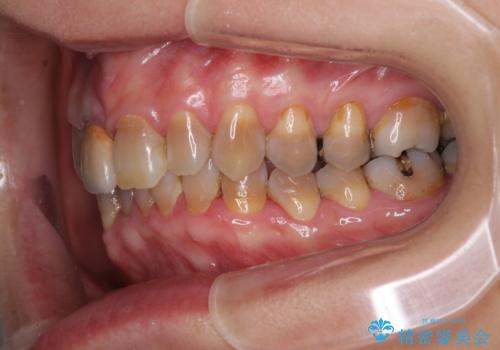

- 前歯のデコボコと、顎に負担のかかる歯並びを改善したいとのことで来院された患者様です。

うまく歯ぎしりができず、強く食いしばりをしてしまう咬み合わせであったため、奥歯に非常に負担がかかっていました。

インビザラインを用いて前歯のデコボコを改善するとともに、奥歯の咬み合わせを変えてスムーズに歯ぎしりできるように排列していくこととしました。

可能であれば上下正中を合わせ、左右の咬み合わせも改善したかったのですが、骨格的な左右差が大きかった上に、インビザラインでは限界があり、達成できませんでした。

それでも奥歯の負担を改善することができました。